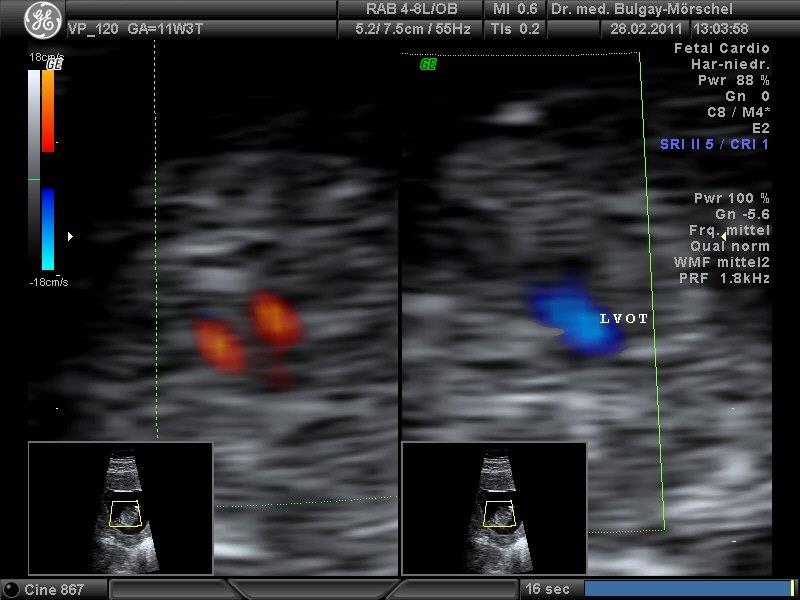

Die fetale Echokardiografie ist die detaillierte Untersuchung des kindlichen Herzens mittels hochauflösender Ultraschallgeräte. Hierbei können z.B. die Herzklappen, Herzhöhlen, die großen Gefäße des Herzens beurteilt werden. Der Blutfluss im kindlichen Herz kann mit Hilfe der Dopplersonografie sichtbar gemacht werden. Die vorgeburtliche Erkennung fetaler Herzfehler ist für die Geburtsplanung von sehr großer Bedeutung.

Die Dopplersonografie ermöglicht die Messung des Blutflusses in den mütterlichen/kindlichen Gefäßen. Das Blutflussmuster in den Gebärmutterarterien/Nabelschnurarterien kann Auskunft über die Versorgungssituation der Plazenta und des Kindes (z.B. bei Plazentainsuffizienz) geben. Veränderung der Blutflussgeschwindigkeit in den fetalen Hirngefäßen kann ein Hinweis auf kindliche Blutarmut sein.